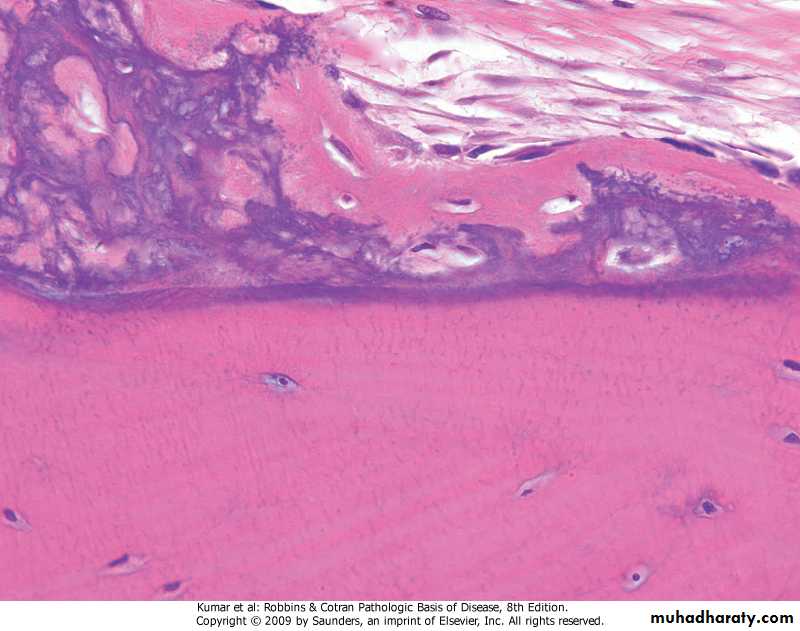

Osteoclasts resorbingboneWoven bone (top) deposited on surface of lamellar bone

Woven bone (top) deposited on surface of lamellar bone